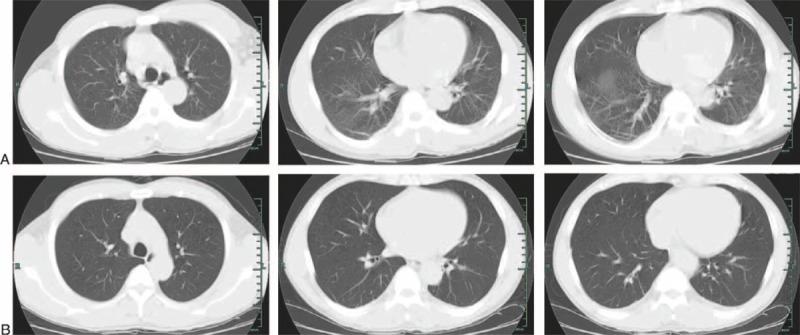

We described and analyzed the treatment process of an HIV-positive patient with severe paraquat (PQ) poisoning. A 34-year-old man ingested about 50 mL of a 20% solution of PQ in a suicide attempt. He was treated with gastric lavage, oral administration of adsorbent, and symptomatic treatments at the local hospital, and was transferred to our emergency department. Ten hours after the exposure, the concentration of plasma PQ was 2.17 mg/L and was substantially above the survival limits of the severity index for PQ poisoning (SIPP) curve (0.30 mg/L). The equation produced by Jones et al (Jones AL, Elton R, Flanagan R. Multiple logistic regression analysis of plasma paraquat concentrations as a predictor of outcome in 375 cases of paraquat poisoning. QJM. 1999:92;573-578) predicted a 20.5% probability of survival at admission. Unfortunately, the patient was diagnosed as HIV infected, and CD4 lymphocyte count also confirmed that the patient was in a state of mild suppression of immunological function. Immediately, the patient received normative immunosuppressive therapy and hemoperfusion (HP). On the 15th day after poisoning, the patient recovered well and was discharged. All along, the evolution of the patient's status was in accordance with the characteristics of PQ poisoning, but the extent and duration of damage was mismatching and drastically alleviative by the previous biological indices. The particular case of treatment may be indirectly supporting the effectiveness of immunosuppressive therapy in treating patients with PQ poisoning.

我们描述并分析了一名HIV阳性患者严重百草枯(PQ)中毒的治疗过程。一名34岁男性为自杀吞服了约50毫升20%的PQ溶液。他在当地医院接受了洗胃、口服吸附剂及对症治疗,随后被转至我院急诊科。接触PQ 10小时后,血浆PQ浓度为2.17毫克/升,显著高于PQ中毒严重程度指数(SIPP)曲线的生存极限(0.30毫克/升)。Jones等人(Jones AL, Elton R, Flanagan R. Multiple logistic regression analysis of plasma paraquat concentrations as a predictor of outcome in 375 cases of paraquat poisoning. QJM. 1999:92;573 - 578)得出的方程预测入院时生存概率为20.5%。不幸的是,该患者被诊断为HIV感染,CD4淋巴细胞计数也证实患者处于免疫功能轻度抑制状态。随即,患者接受了规范的免疫抑制治疗及血液灌流(HP)。中毒后第15天,患者恢复良好并出院。一直以来,患者病情的演变符合PQ中毒的特征,但损伤的程度和持续时间并不匹配,且较之前的生物学指标大幅减轻。该特殊治疗案例可能间接支持了免疫抑制疗法在治疗PQ中毒患者中的有效性。